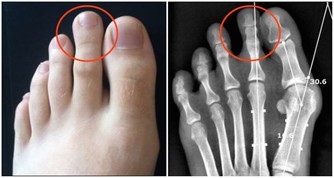

如果你天天熬夜到 1 點多,肝回不了血,有毒的血排不掉,新鮮的血生不成,膽又無法換膽汁,

所以這些人容易得膽結石、囊腫、大三陽、小三陽各種病癥。